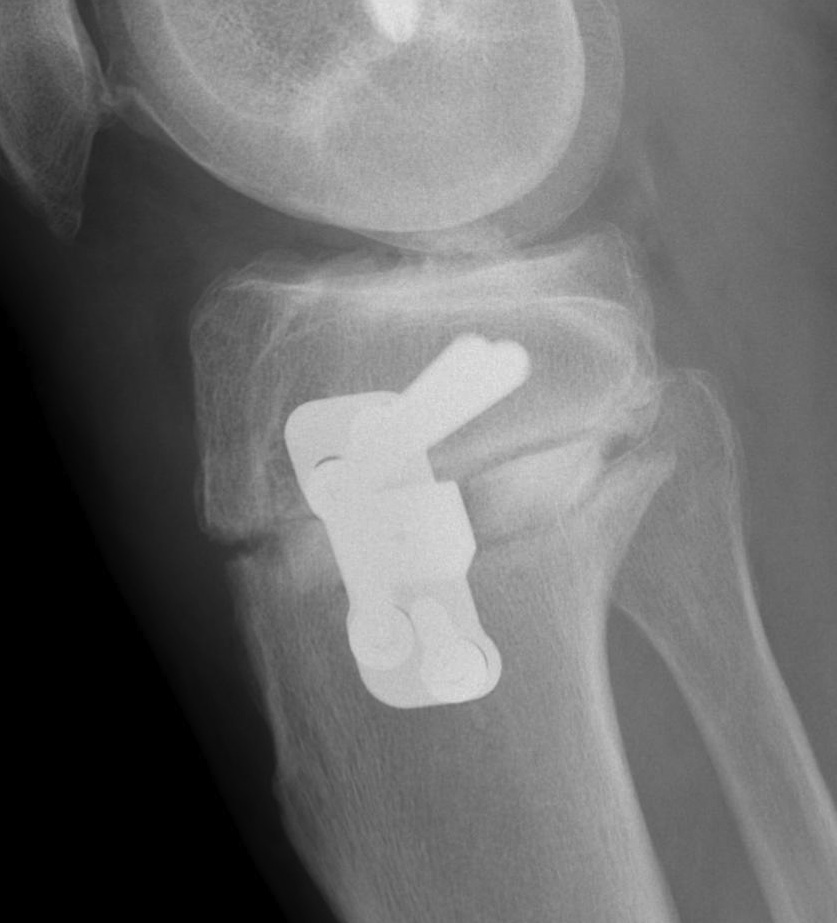

- ensure osteotomy is parallel to joint line to avoid altering slope

Guide pins for osteotomy and checking posterior slope

- ensure no change of posterior slope on lateral

Stabilisation

- locking plates

- +/- autograft / allograft / synthetic bone graft

Arthrex Locking Puddhu plate PDF

Arthrex ContourLock system PDF